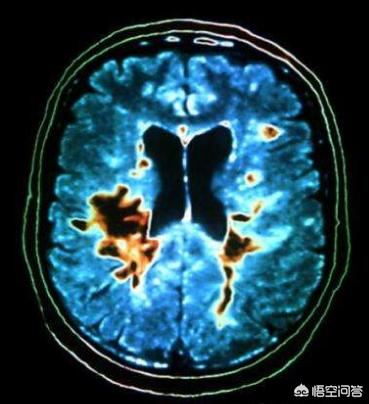

脳梗塞は脳血管以外では非常に一般的で、中高年の容赦ない殺人者である!脳梗塞の危険性は、死亡だけでなく、障害を負う割合が高いことにある!脳梗塞は急速に発症し、さらに急速に進行する!視覚的に理解していただくために、次の図をご覧ください。

👆👆👆 这是脑梗死的缺血半暗带,脑组织缺血1分钟组织就开始缺血氧,脑细胞开始发生变化。したがって、脳梗塞患者は時間との戦いの中にあり、生存率が高く障害率が低い場合は速く走り、生存率が低く障害率が高い場合は遅く走ることになる!